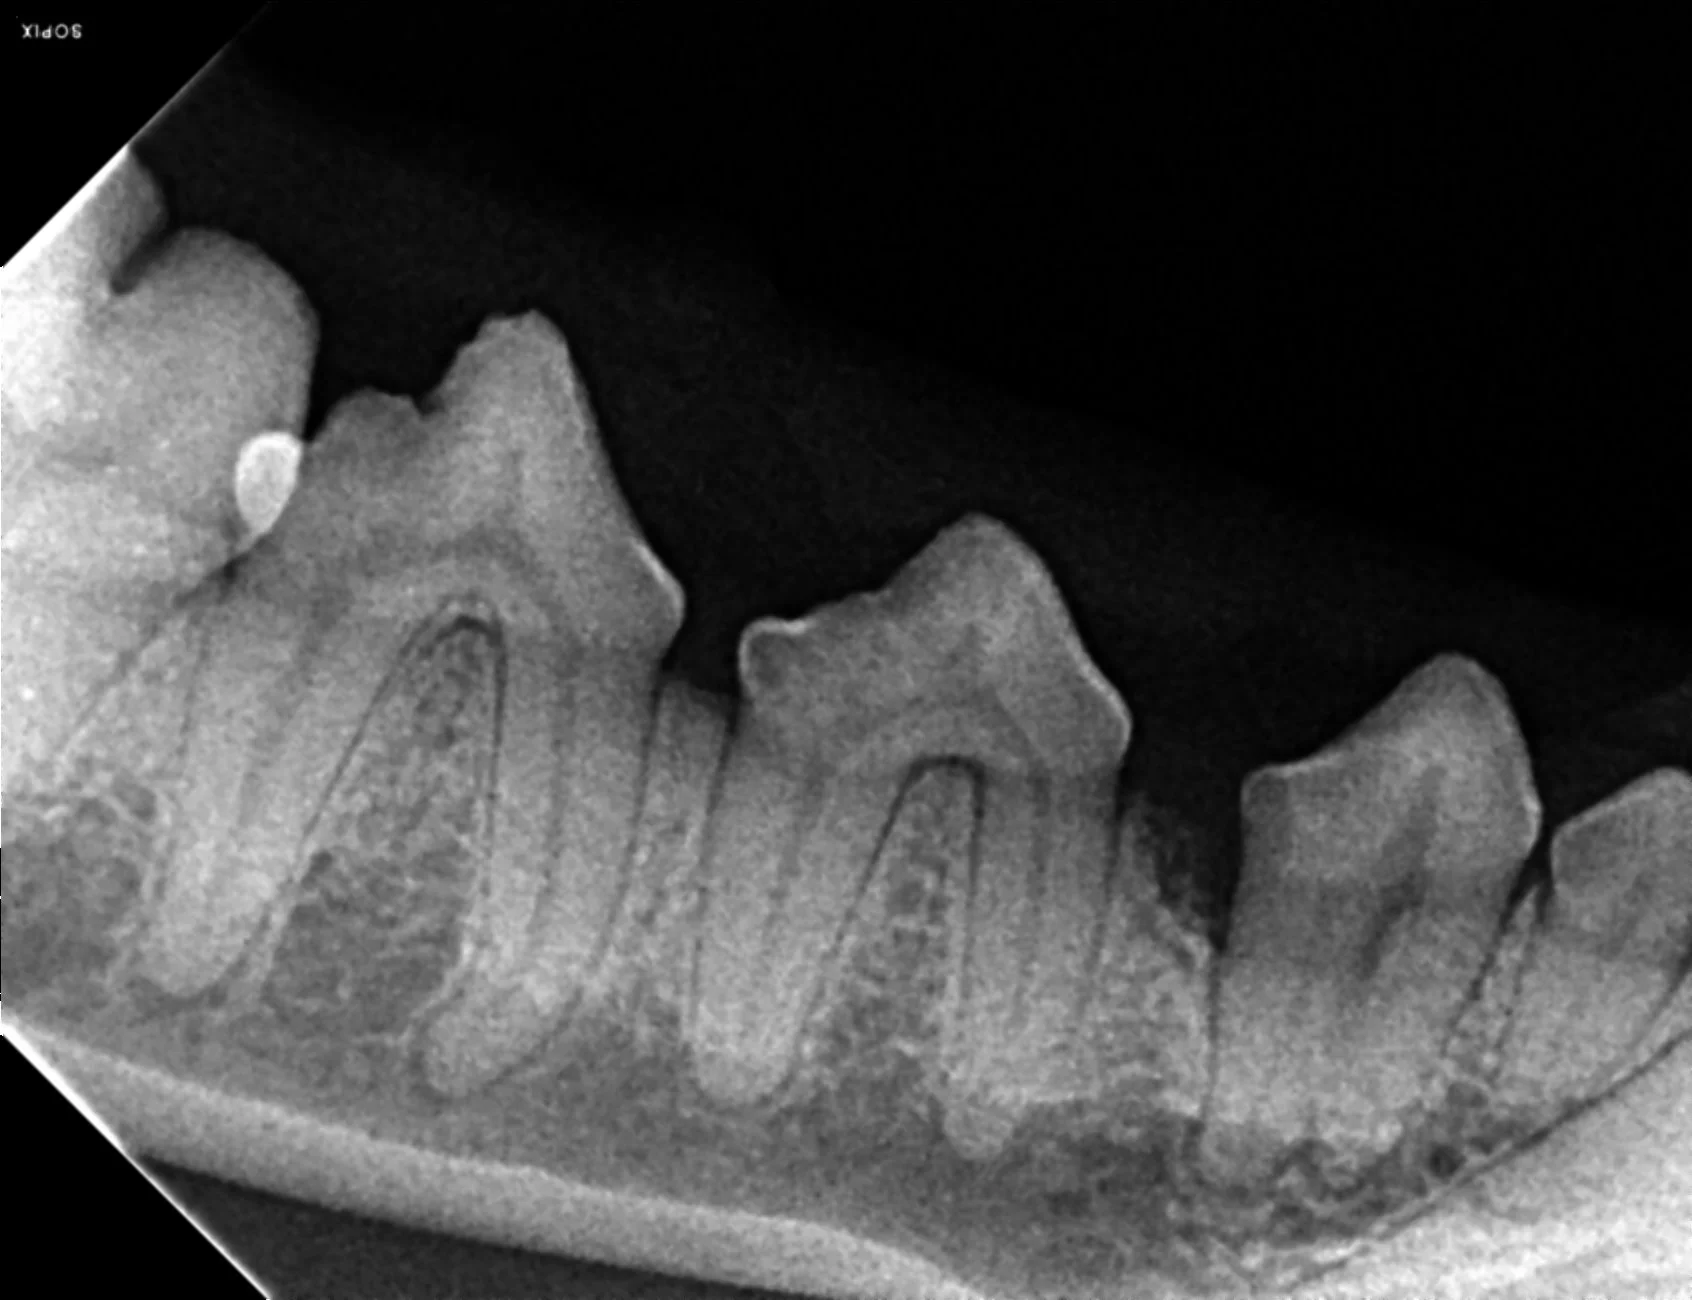

The prophylactic dental includes x-rays of all the teeth, ultrasonic scaling of the plaque and tartar from the teeth, polishing, and fluoride treatment. It is impossible to determine the full extent of dentistry your pet needs until they are under anesthesia and we can examine each tooth individually, but we can give an estimate of your pets dental status and needs during your routine exam.